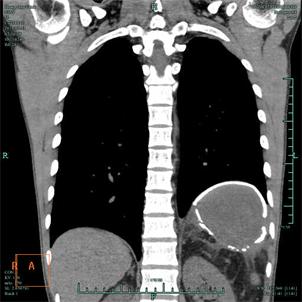

近日我科收治了3例在多家医院无法确诊的疑难病例,均在接诊后第一时间通过介入或者影像技术确诊。上月初我科收治一右侧肺门肿大的患者,该患者既往有淋巴瘤病史,曾在我市多家医院就诊,无法探明肿块具体病因,后转至上海某著名医院,对肿块进行了经皮肺穿刺活检,但仍然无法确诊,后求诊我院,我科俞万钧书记,彭卫东主任等在接诊后第一时间对其进行支气管镜检查,同时凭临床经验行TBLB,对肿块进行定位活检,1周后患者病理证实鳞癌。上月中旬,又一患者慕名来至我科,要求确诊病因。该患者为一老年男性,左侧肺部靠近肺动脉处发现2个结节,我市多家市级医院通过支气管镜等手段无法确诊,后转至上海某著名专科医院,仍然无法确诊,后经人介绍,至我科,我科俞万钧书记,彭卫东主任等制定经皮穿刺方案,因病灶靠近肺动脉,我科在CT室李胜主任的协助下,凭借丰富临床经验取得活检标本,证实肿块为结核,患者感激涕零。本月初,一中年男性因发热1月余,来我院就诊,在我院就诊前,该患者先后就诊于我市多家县市医院,后转至杭州专科医院,均无法确诊,患者万般无奈,承受着肉体和精神的煎熬,来我科就诊。第二天,查房,我科俞万钧书记,彭卫东主任,徐涛副主任医师等通过读片,重点怀疑是患者的腹部炎症感染,通过CT室李建斌医师的帮助,对患者的病灶进行三维重建,确诊患者为膈下慢性脓肿,DSA马霁波医师进行穿刺,引流出脓液将近1000ml,患者体温渐渐恢复正常,目前患者康复中。我科近年来,特别是去年以来,在俞万钧书记的带领下,呼吸介入水平突飞猛进,同时积极寻求多科合作,和我院肿瘤放化疗科,影像科,CT室,病理科等保持密切合作,共进互助,努力为患者解除病魔痛苦,更好地为人民健康服务。(徐涛)